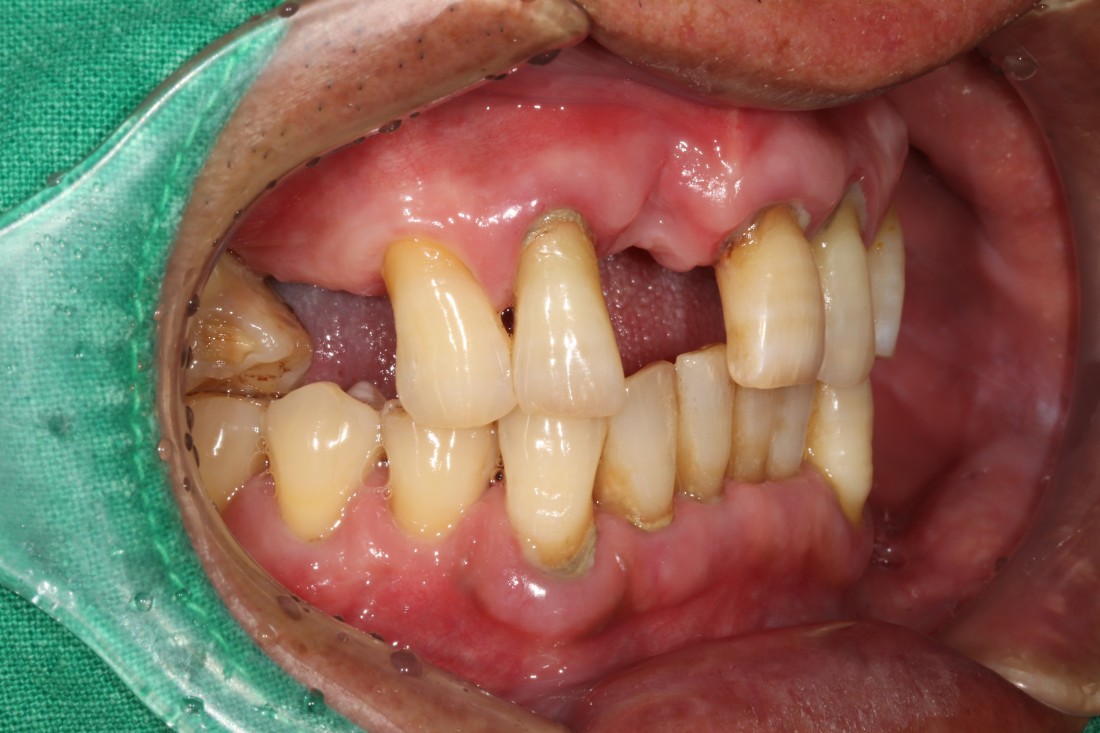

광주 앞니임플란트

구강외과 전문의가

직접 진료하나요?

광주 앞니임플란트치과의

앞니 임플란트 치료원칙 3가지는

1. 안 아프게

2. 예쁘게

3. 잘 씹어지게

입니다.

모든 치과에서 디지털 가이드 임플란트가

가능한 것이 아니고,

최첨단 기기를 갖춘 환경이 있어야 합니다.

또한, 모든 치과의사가 디지털가이드 임플란트

식립 경험이 풍부한 것이 아니기 때문에

디지털 가이드 임플란트로

앞니 임플란트 식립 경험이 많은

광주 앞니 임플란트 치과의

구강외과 전문의 원장님 진료를

받으셔야하는 이유입니다.